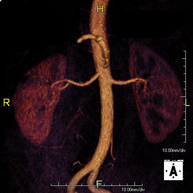

Prueba diagnóstica no invasiva que consiste en la obtención de imágenes de alta definición anatómica de todo el cuerpo mediante el empleo de un campo electromagnético y ondas de radio (con un emisor y un receptor). No utiliza radiación ionizante. Es una prueba muy importante en la búsqueda de metástasis en pacientes con neoplasia conocida. No requiere preparación previa. No es necesario el empleo de contraste paramagnético (Gadolinio). - Angio-RM Aorta abdominal

Prueba diagnóstica no invasiva que consiste en el estudio de la arteria aorta abdominal, obteniendo imágenes de alta definición anatómica mediante el empleo de un campo electromagnético y ondas de radio (con un emisor y un receptor). Es indispensable el uso de contraste paramagnético (Gadolinio). Sin embargo, no utiliza radiación ionizante. La calidad de las imágenes permite realizar reconstrucciones en 2D y 3D. Está indicado en aquellos pacientes con enfermedad vascular (aterosclerosis), estudio de aneurismas, en estudios pre-quirúrgicos de lesiones adyacentes a la aorta abdominal como "mapa" vascular, etc. - Angio RM Aorta-ilíaca